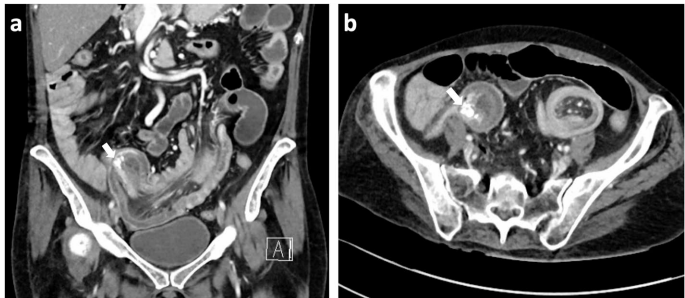

实验室检查显示C反应蛋白(CRP)轻度升高(29 mg/l),血红蛋白和白细胞计数正常。CT影像发现一长达20 cm的回盲部肠套叠,导致小肠梗阻,并识别出一个17 mm钙化肿块作为引导点。

由于肠套叠范围广泛,腹腔镜手术不可行,遂行开腹手术。术中发现小肠套入盲肠,引导点为一可触及的肿块,距回盲瓣30-45 cm。行小肠楔形切除及淋巴结 dissection,并行侧侧吻合术。

切除标本为一段长100 mm、直径40 mm的小肠,可见套叠和浆膜撕裂。肿块为15 mm钙化结节,距切缘80 mm。